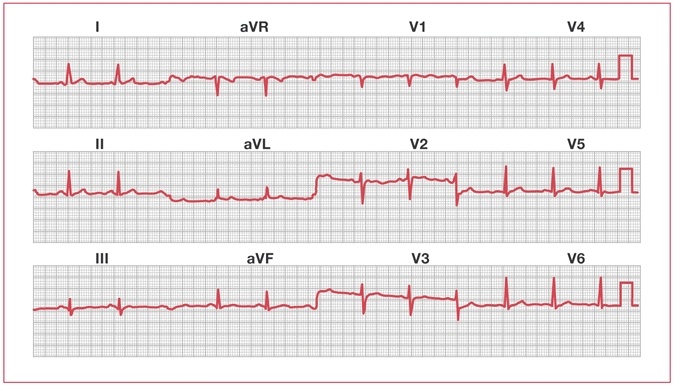

Для регистрации электрических потенциалов сердца на коже фиксируются электроды. В результате получается поймать сигнал, отображающий сердечные циклы, — ЭКГ (электрокардиограмма). Один нормальный период ЭКГ состоит из 3 волн: P, QRS и T, которые несут в себе разную информацию.

• Волна P связана с деполяризацией предсердий, то есть с электрическим возбуждением их клеток, за которым следует механическое действие — сокращение предсердий.

• Волна QRS отвечает за деполяризацию желудочков, их электрическую активность перед сокращением.

• Волна T — характеристика реполяризации желудочков, когда клетки возвращаются в состояние покоя и происходит расслабление.

Рисунок волн, интервалы между ними — эти параметры выражают процессы, которые протекают в сердце, и, читая линии, можно заметить нарушение каких-то функций органа. Например, пилообразная форма волны P указывает на трепетание предсердий.